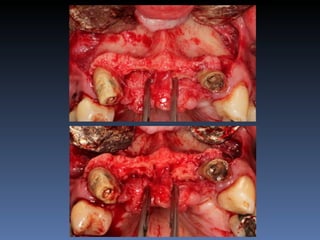

BOX 5

Maria Gomes Moraes

Idade – 53 anos

Sexo – Feminino

Raça – Caucasiana

ASA – II

Data- 23-04-2012

Diagnóstico: Atrofia severa

da pré-maxila.

Plano de tratamento: Aumento de volume horizontal

com blocos ósseos autógenos “onlay” provenientes do

Ramus da Mandíbula.

sutura nylon 4-0

Pós-operatório -5 dias